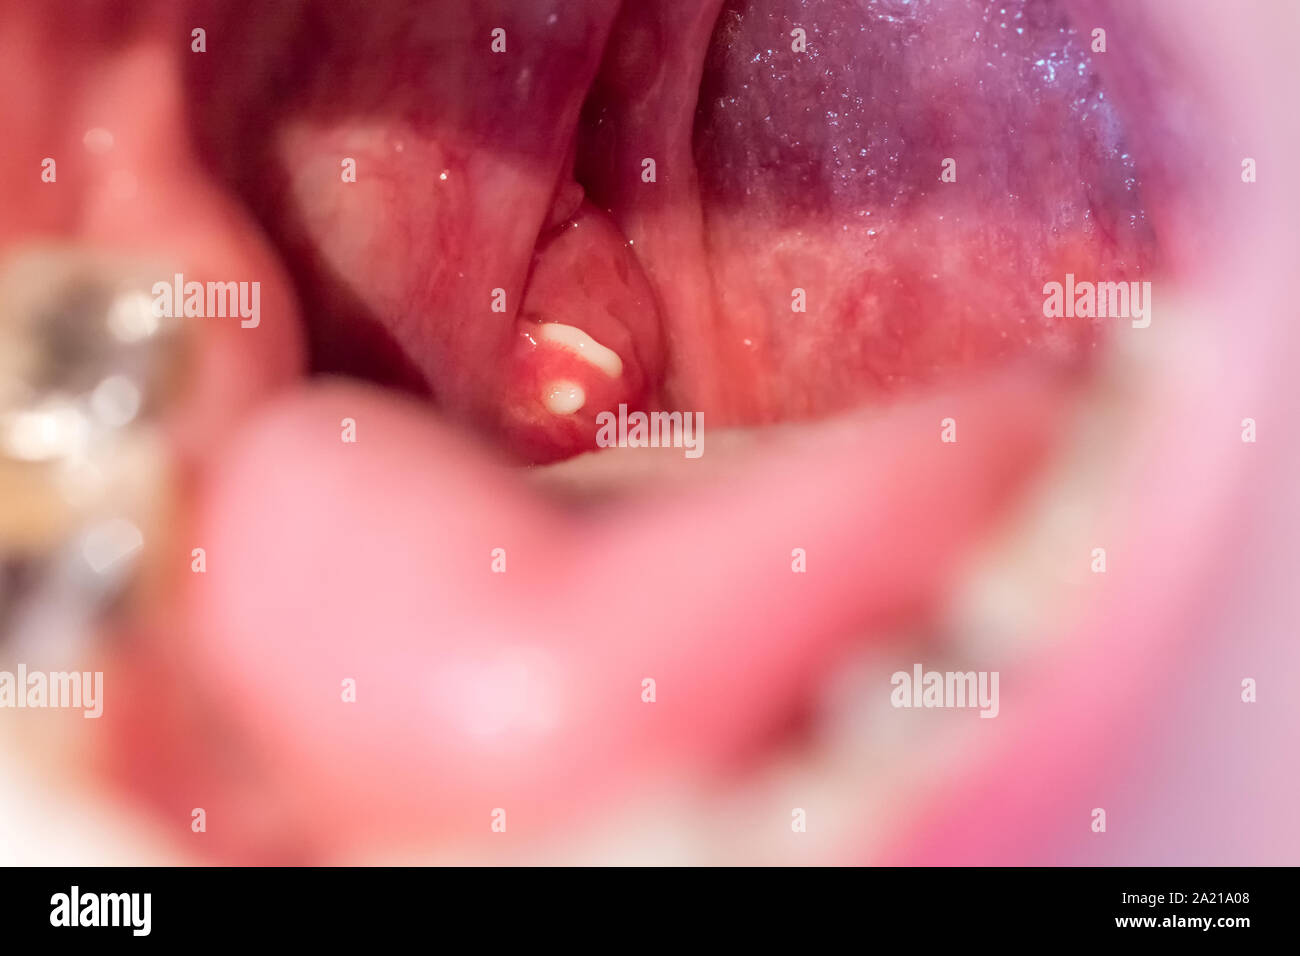

Weiße Mandel Steine auf die gaumenmandeln als Auslöser des schlechten Atems Stockfotohttps://www.alamy.de/image-license-details/?v=1https://www.alamy.de/weisse-mandel-steine-auf-die-gaumenmandeln-als-ausloser-des-schlechten-atems-image328256104.html

Weiße Mandel Steine auf die gaumenmandeln als Auslöser des schlechten Atems Stockfotohttps://www.alamy.de/image-license-details/?v=1https://www.alamy.de/weisse-mandel-steine-auf-die-gaumenmandeln-als-ausloser-des-schlechten-atems-image328256104.htmlRF2A21A08–Weiße Mandel Steine auf die gaumenmandeln als Auslöser des schlechten Atems